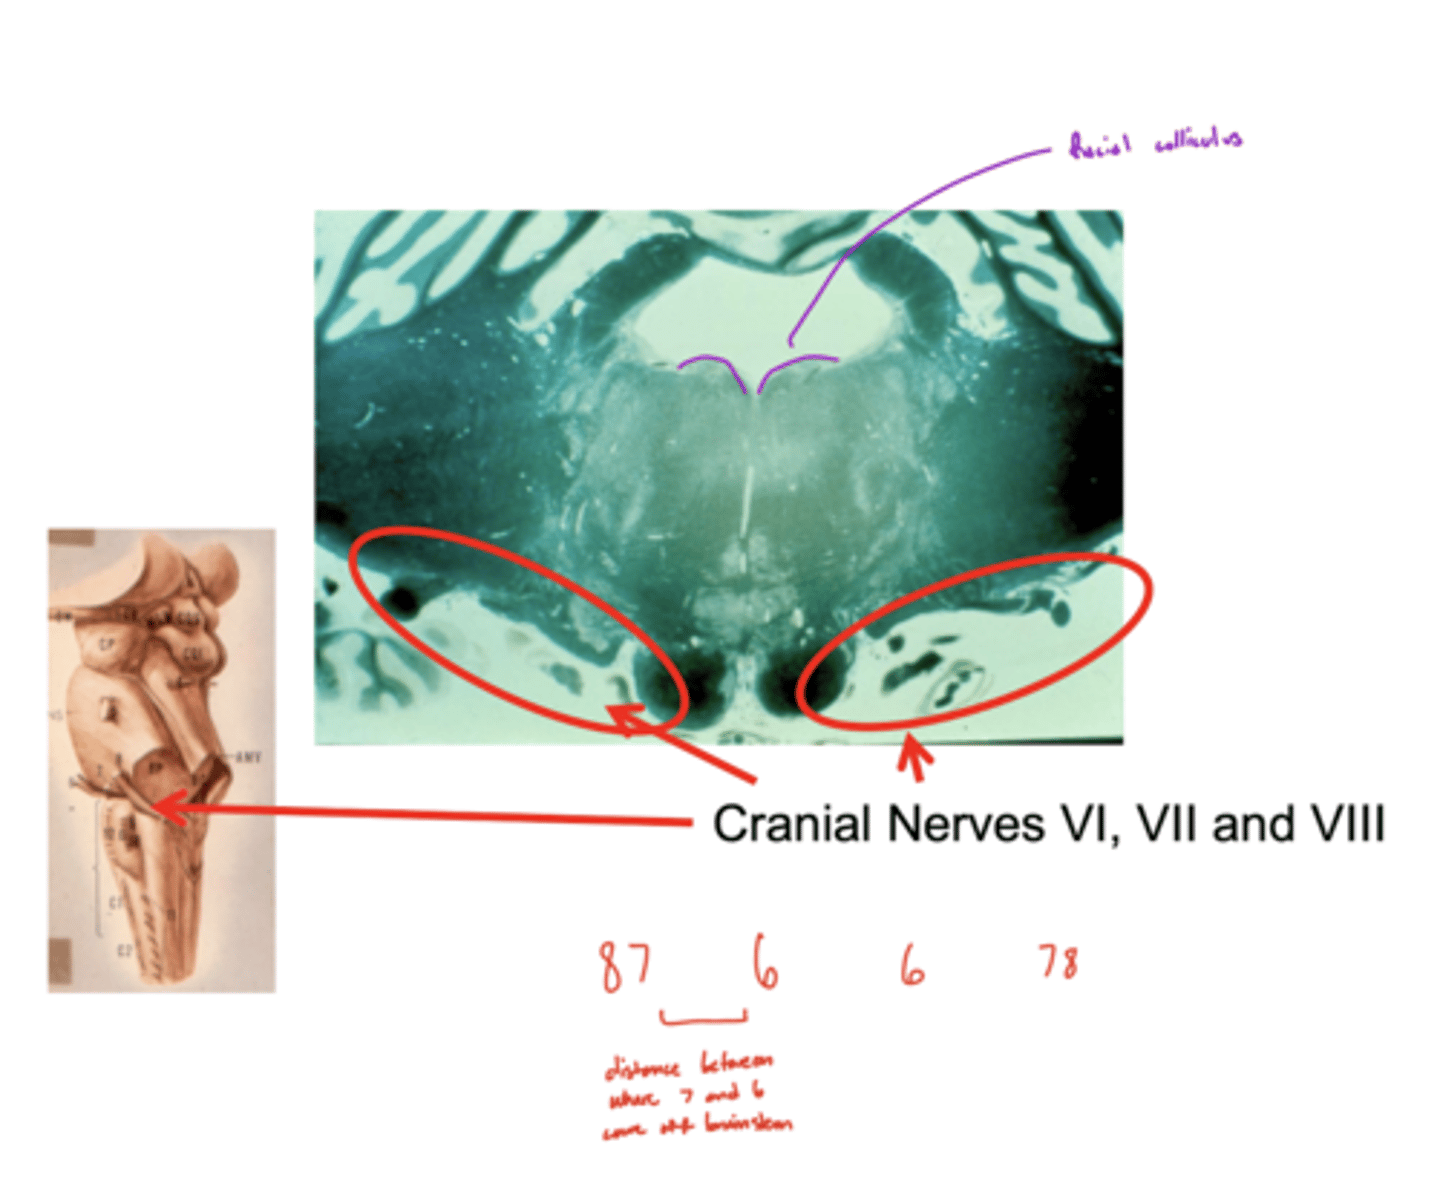

What are the facial colliculi?

bumps (hills) coming out from dorsal pontomedullary junction into the 4th ventricle -- CN VII SVE fibers create this space when they wrap around the abducens nucleus

Where do CN VI, VII, VIII exit the pons?

pontomedullary junction

What is the spacing of CN VI, VII, and VIII exiting the pontomedullary junction?

8 & 7 -- lateral and closer together

6 -- medial and far away

image -- look at red font